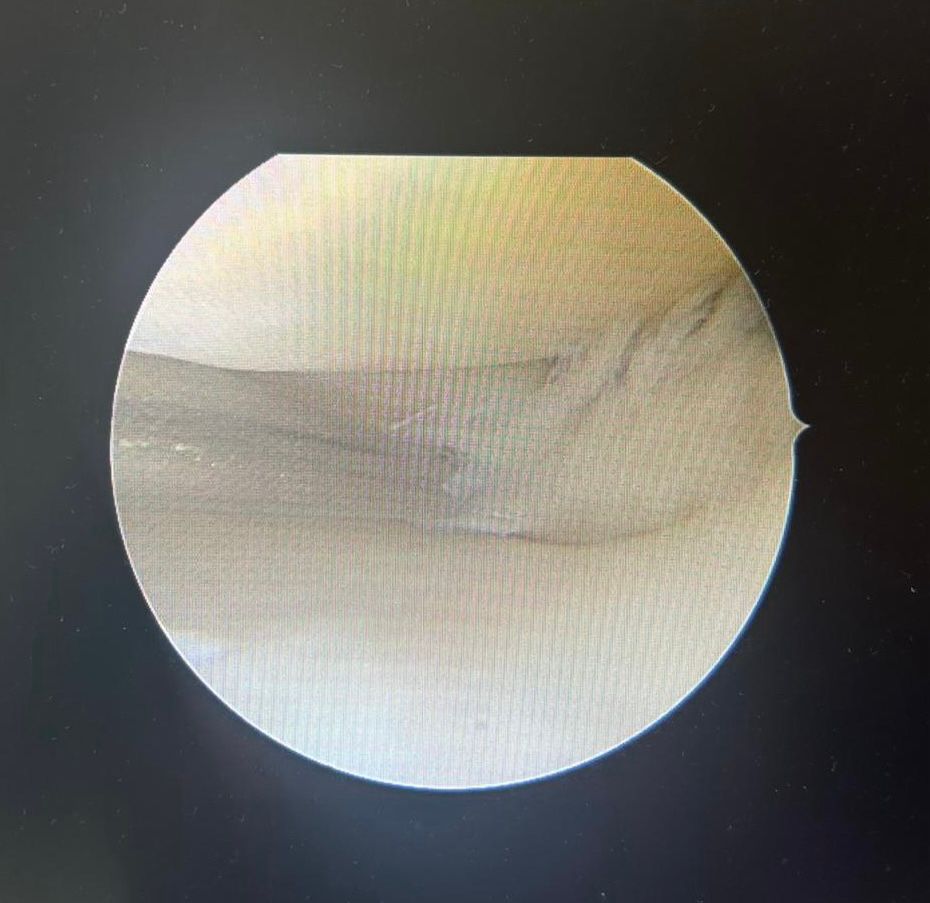

Hier ein Beispiel für einen eingeschlagenen Meniskus Riss , der sich immer in den Gelenkbereich innen eingeschlappert hat . Ein Befund der einen Minimal-invasiven Eingriff rechtfertigt.